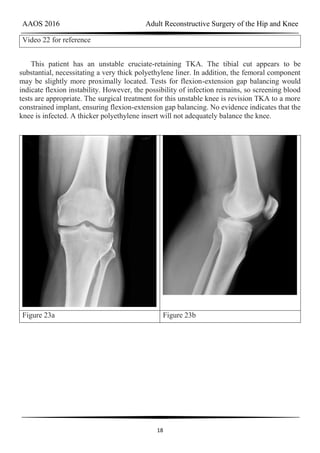

Figure 23a Figure 23b

DISCUSSION

AAOS 2016 Adult Reconstructive Surgery of the Hip and Knee

18

Video 22 for reference

This patient has an unstable cruciate-retaining TKA. The tibial cut appears to be

substantial, necessitating a very thick polyethylene liner. In addition, the femoral component

may be slightly more proximally located. Tests for flexion-extension gap balancing would

indicate flexion instability. However, the possibility of infection remains, so screening blood

tests are appropriate. The surgical treatment for this unstable knee is revision TKA to a more

constrained implant, ensuring flexion-extension gap balancing. No evidence indicates that the

knee is infected. A thicker polyethylene insert will not adequately balance the knee.